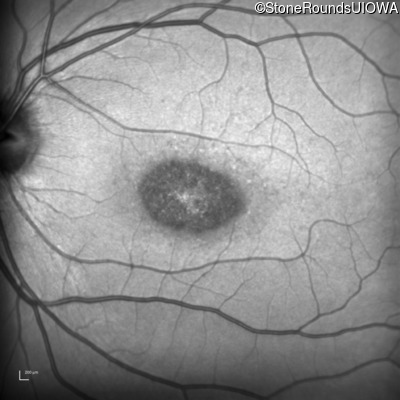

Infrared Fundus Photograph - Right - 20/125 sc

Exemplar